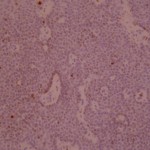

Ki-67 staining of an acantho-hyperkeratotic type of SK. On the last picture, most of the basal staining comes from the accumulation of pigment as the clinical image suggests.

Ki-67 staining of an acantho-hyperkeratotic type of SK. On the last picture, most of the basal staining comes from the accumulation of pigment as the clinical image suggests.

Ki-67 staining of an acantho-hyperkeratotic type of SK. On the last histological picture, most of the basal staining comes from the accumulation of pigment as the clinical image suggests.